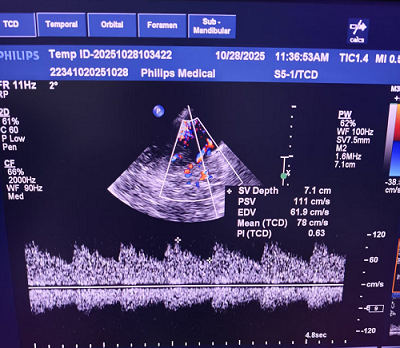

TCCD 频谱图